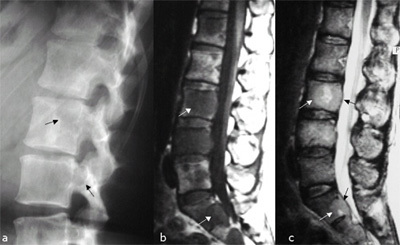

HÉRNIA DE DISCO

Degeneração/fraqueza do ânulo fibroso, fazendo extravazar núcleo pulposo, comprimindo raiz nervosa (sensitiva mais comum)

Local mais comum de acometimento: L4-L5 e L5-S1

Clínica: lombociatalgia irradiada, diminuição de força (raiz motora), sensibilidade (raiz sensitiva) e reflexos (segundo neurônio)

Sinal de Laségue positivo

Diagnóstico: RNM

Tratamento: repouso, analgesia, corticoide, cirurgia